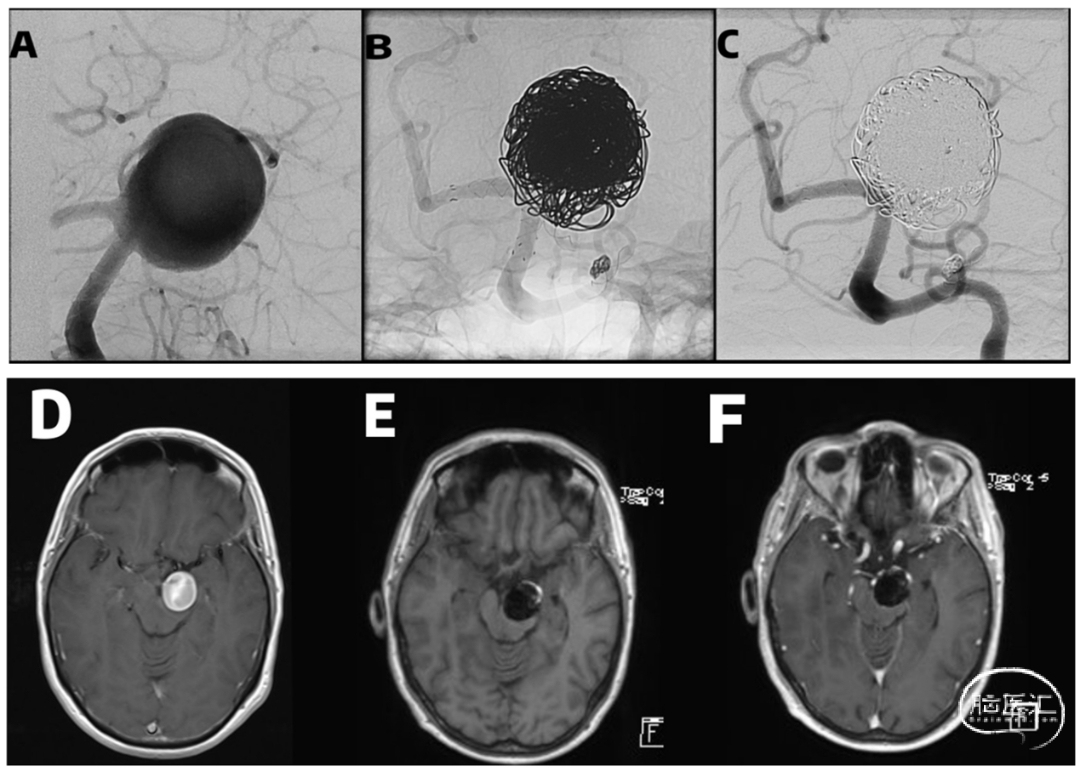

Figure 3. Giant superior cerebellar artery (SUCA) aneurysm treated with balloon-assisted coiling and Complete-T stenting. A, Initial digital subtraction angiography demonstrating a 28-mm aneurysm. B and C, Unsubtracted and subtracted angiographic images at 12-month follow-up confirming complete occlusion (Raymond Roy Class I). D, Axial post-contrast T1-weighted MR image before treatment. E and F, Axial pre- and post-contrast T1-weighted MR images at 12-month follow-up demonstrating stability without growth or wall enhancement.

唯一死亡病例:Complete-T组1例巨大动脉瘤(28mm)使用FRED FD,术后动脉瘤再通、脑干压迫,14个月死亡——提示FD在SUCA巨大动脉瘤中风险极高。